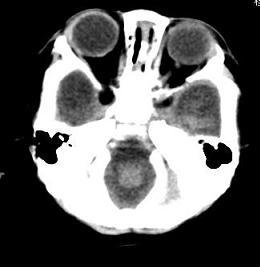

男,4个月大,2个月前无诱因下四肢抽搐、伴呕吐,近2天来抽搐频发,伴发热。查体:双眼疑视,神萎、纳差;颈抵抗,四肢张力高。

病史太长了,原因不好定,不过如果2个月前小儿正常的话可考虑积水型无脑畸形,积水型无脑畸形小儿刚生下来表现可正常,存活一两个月后出现症状.

另不除外缺血缺氧性脑病,感染等改变

2个月前缺血缺氧性脑病留下的后遗症。

脑出血后,软化灶形成了。脑发育不良

支持缺血缺氧性脑病留下的后遗改变(脑软化灶+脑发育不全+双侧慢性硬膜下积液+小头畸形)。

要注意化脓性脑膜、脑炎,硬膜下积脓,脑积水的可能,建议腰穿助诊。